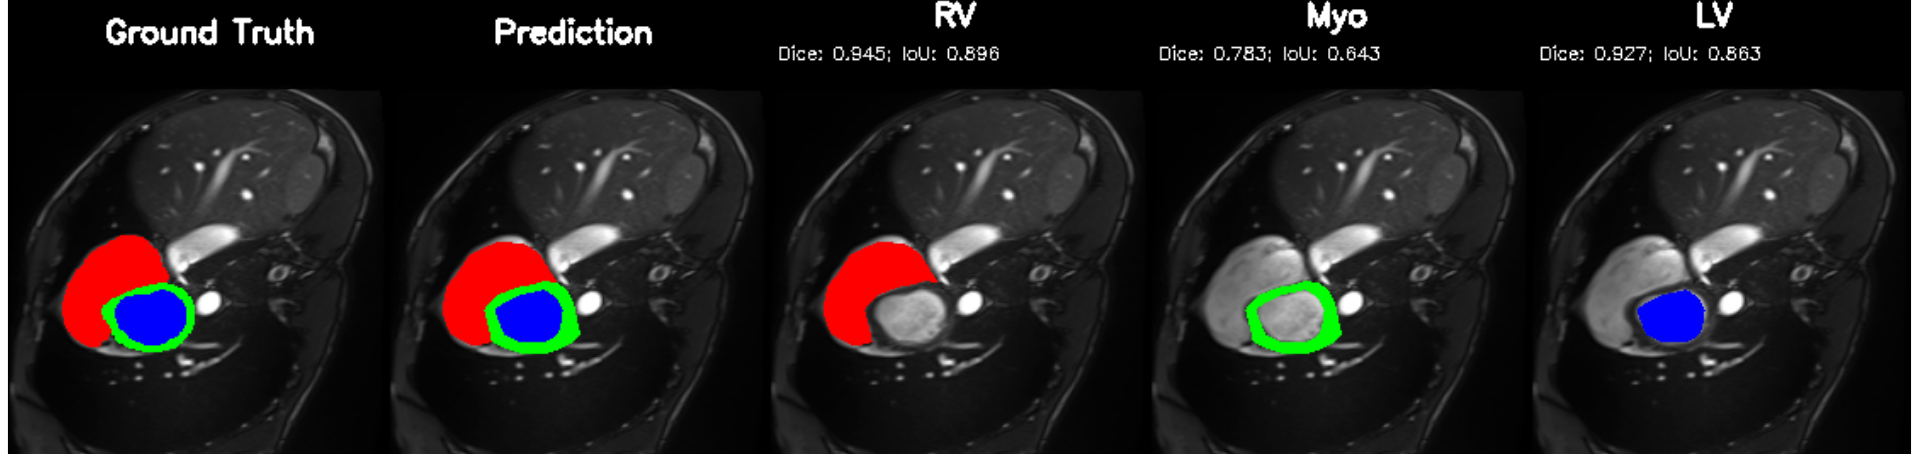

5.2 M&Ms Cine-MRI Generalization

Figure 8 illustrates segmentation outputs on the M&Ms (Multi-Centre, Multi-Vendor) cine-MRI dataset, which exhibits both contrast variation and vendor–specific acquisition differences compared to ACDC. The model retains consistent ventricular geometry, recovering LV and Myocardium structure without retraining, mirroring the zero-shot Dice performance of 74.8% (Table 11). Boundary thickness remains physiologically accurate, with only minor degradation in the right ventricle, an expected behaviour under cross-domain shifts and also reflected quantitatively in the ablation-driven robustness improvements from normalization and loss design. These results demonstrate that PULSE does not overfit to a single scanner distribution but instead transfers cardiac structure priors across unseen clinical environments.